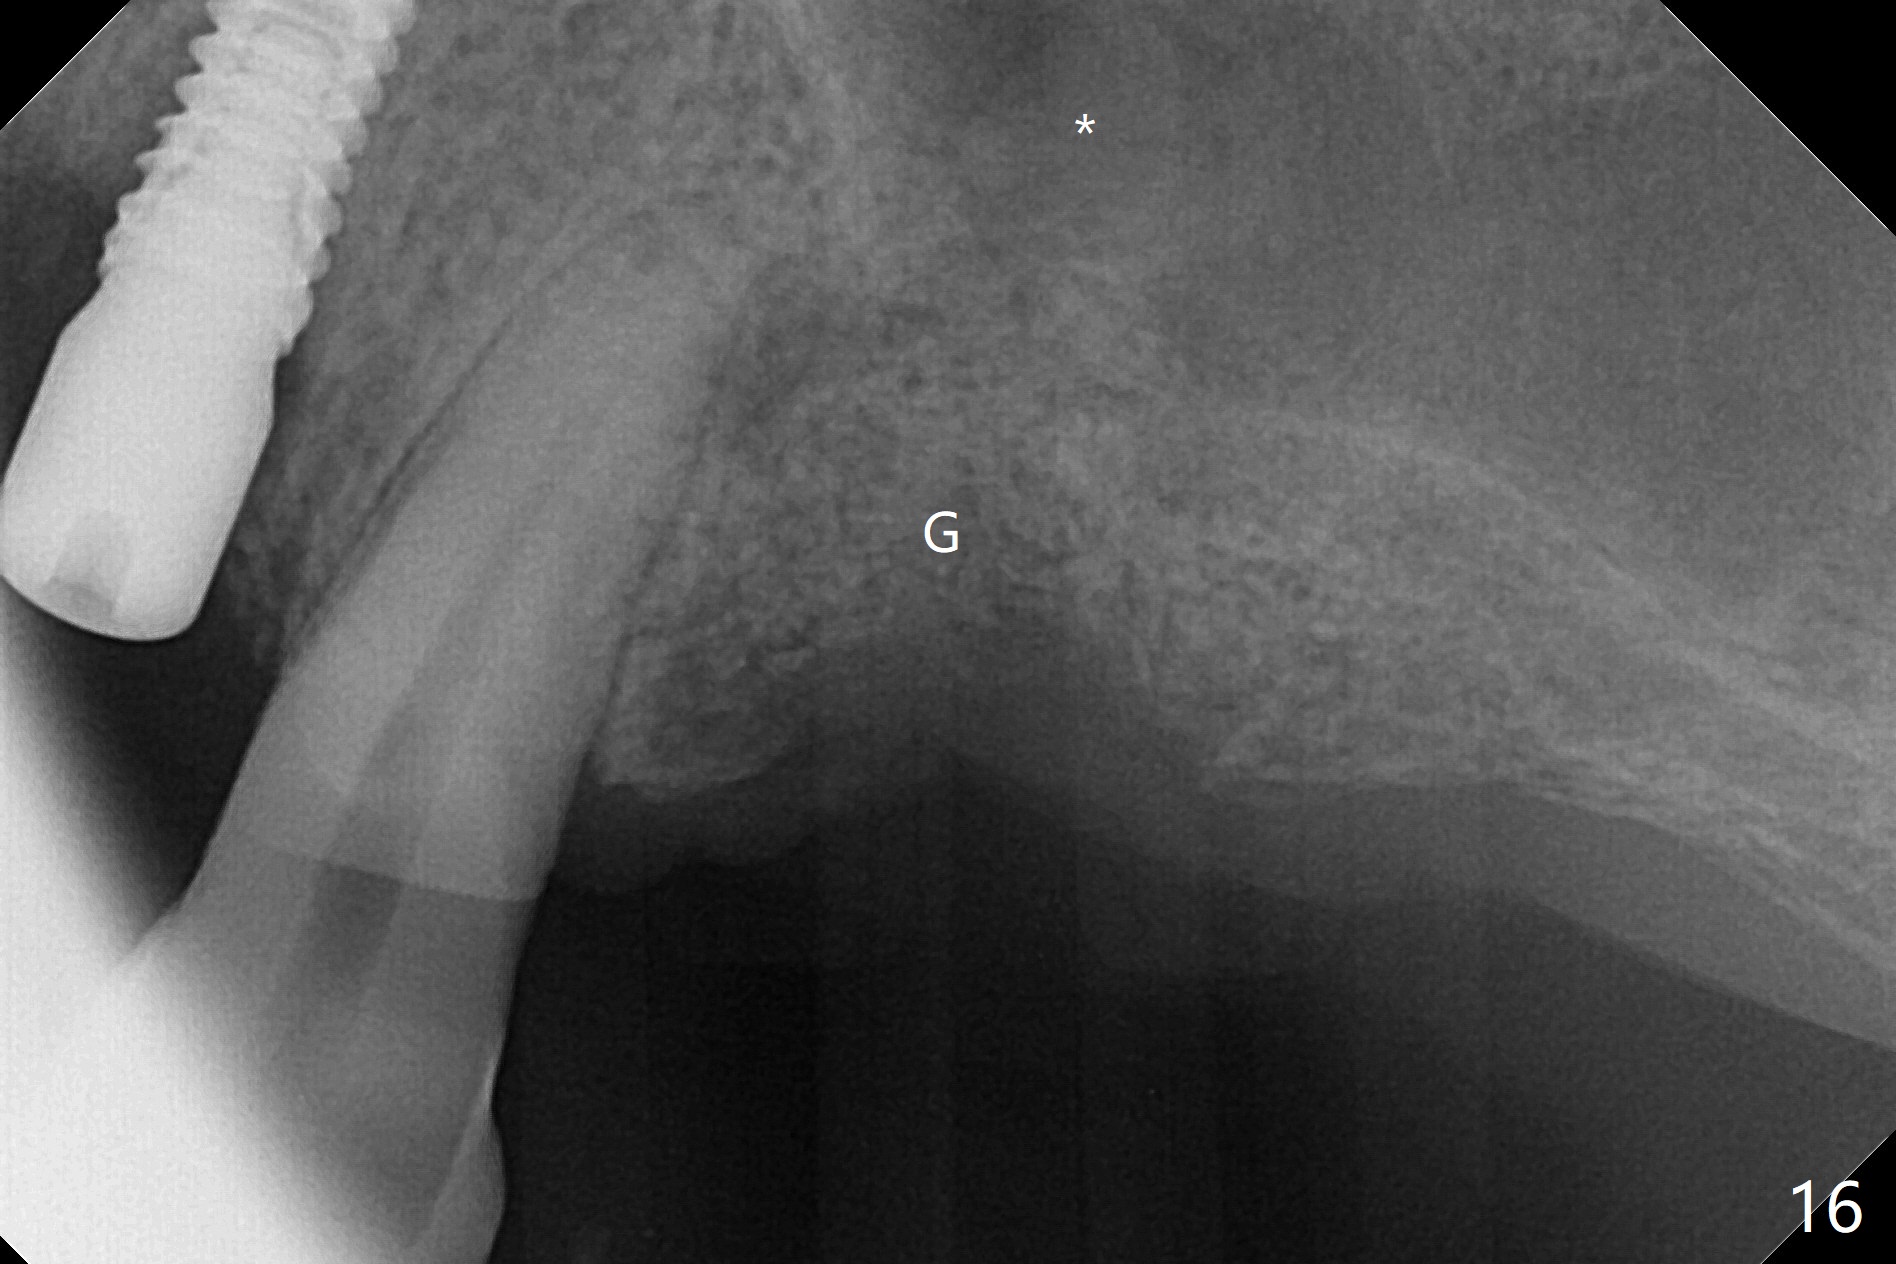

After a 4x10 mm implant is placed with fixture mounting (Fig.2 M) following sinus lift (*) at #12, osteotomy is initiated at #10 (Fig.1 (T: tube of surgical guide)). It appears that the drill (D) has good trajectory (between the Incisive Canal (red dashed line) and the canine root). The final position of the implant at #10 is acceptable (Fig.3). The implant at #12 is placed deeper (Fig.4 (arrow), as compared to Fig.2) because of clinically buccal superficial placement. The most critical challenge is anterior deep bite associated with posterior collapse. Periodontal dressing is applied. When the latter dislodges, there is minimal clearance for a provisional. Periodontal dressing is re-applied. The patient (smoker, partial edentulism with occlusal interference) returns for provisional nearly 1 month postop with chief complaint "something is lost in the back". In fact the healing abutment at #12 is lost with buccal granulation tissue (Fig.5). When a new abutment is seated, there is discomfort. When a healing screw is placed, it cannot be seated completely with two separate trials (Fig.6,7). Should we leave it as it is or open up for complete seating? It appears that the implant is loose. After preparation for clearance at #10, the abutment is retightened. It appears to turn with the underlying implant with discomfort. A 4x5 mm healing abutment is placed to reduce micro-movement. One week later, the infection at #12 dissolves with oral Amoxicillin (Fig.8). Due to limited occlusal clearance and implant tenderness when the abutment abutment is retightened, the cemented abutment is changed to a healing abutment. The implant at #10 seems to be osteointegrated, while the healing screw at #12 remains incomplete seating 3 months postop (Fig.9). The loose healing screw cannot be retightened securely, as there is bone loss around the implant 3 months postop (Fig.10 *). When a 4.5 mm x 15 degree 4 mm cuff angled abutment is placed, the mesiodistal trajectory improves (Fig.11), but there is no occlusal clearance (Fig.12). The latter would form when posterior support is established (Fig.13, either removable appliance (which the patient hates) or fixed one (finance)). Fig.14 shows the unhealed site of #12. Incision confirms the bone loss around the implant, which is removed. Although the sinus floor is absent, there is no membrane perforation. After debridement, allograft mixed with small amount of Osteogen is placed (Fig.15,16 G) and covered with Osteogen plug and 6-month membrane.